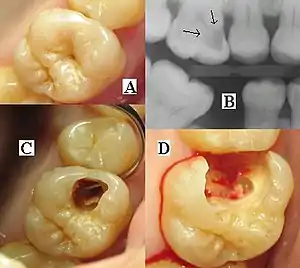

The presentation of caries is highly variable. However, the risk factors and stages of development are similar. Initially, it may appear as a small chalky area (smooth surface caries), which may eventually develop into a large cavitation. Sometimes caries may be directly visible. However other methods of detection such as X-rays are used for less visible areas of teeth and to judge the extent of destruction. Lasers for detecting caries allow detection without ionizing radiation and are now used for detection of interproximal decay (between the teeth).

Primary diagnosis involves inspection of all visible tooth surfaces using a good light source, dental mirror and explorer. Dental radiographs (X-rays) may show dental caries before it is otherwise visible, in particular caries between the teeth. Large areas of dental caries are often apparent to the naked eye, but smaller lesions can be difficult to identify. Visual and tactile inspection along with radiographs are employed frequently among dentists, in particular to diagnose pit and fissure caries.[88] Early, uncavitated caries is often diagnosed by blowing air across the suspect surface, which removes moisture and changes the optical properties of the unmineralized enamel.

At times, pit and fissure caries may be difficult to detect. Bacteria can penetrate the enamel to reach dentin, but then the outer surface may remineralize, especially if fluoride is present.[90] These caries, sometimes referred to as "hidden caries", will still be visible on X-ray radiographs, but visual examination of the tooth would show the enamel intact or minimally perforated.